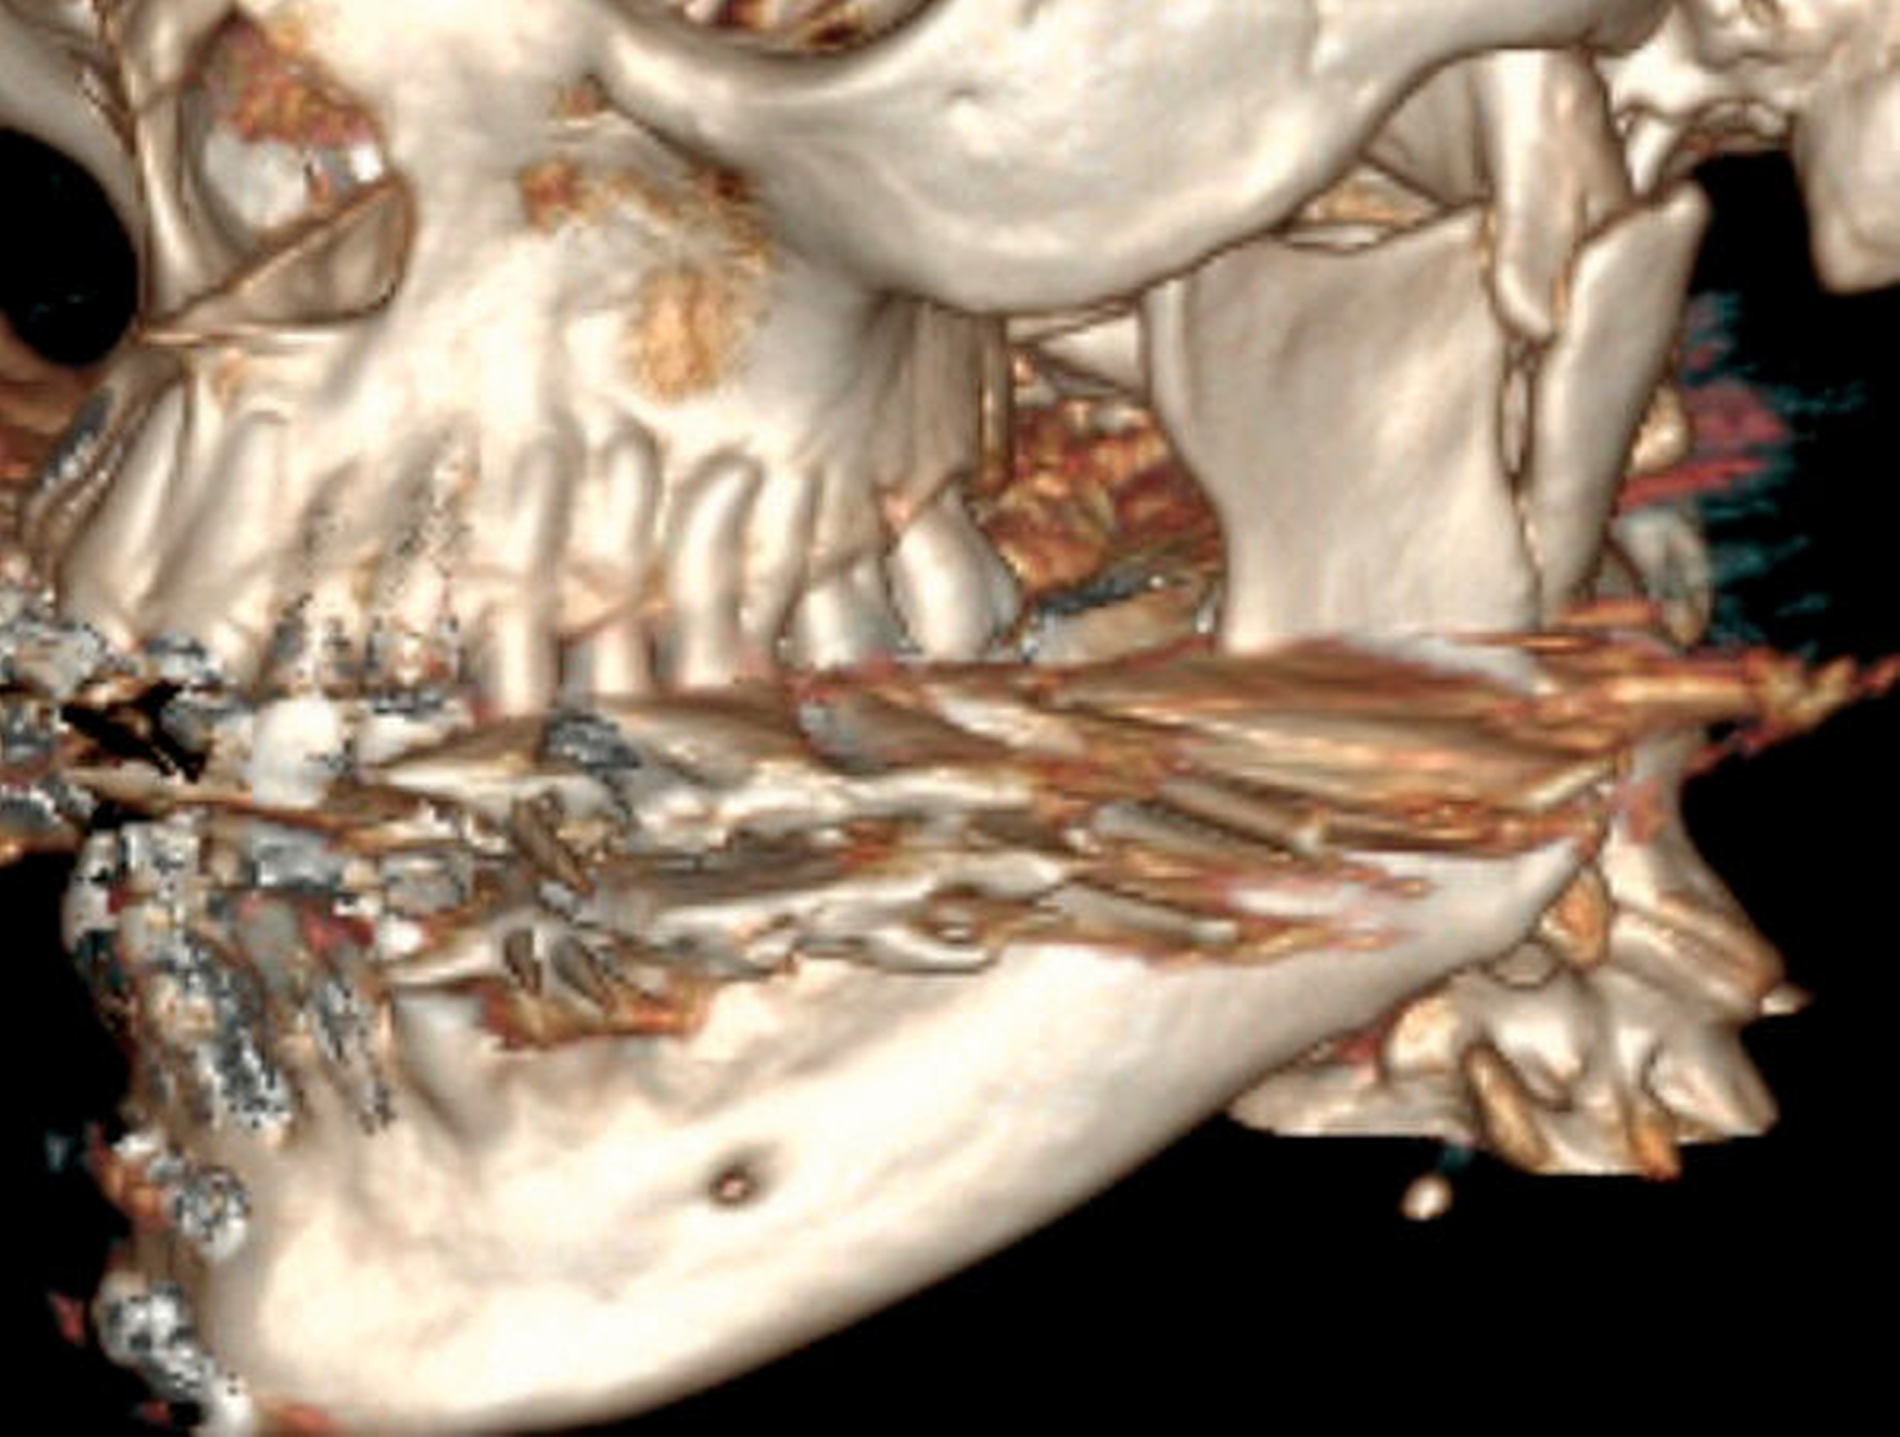

Die Patientin war sehr verängstigt, da sich die Situation immer weiter verschlechterte, ihr Biss sich also immer mehr verschob. Insbesondere beklagte sie die kaufunktionelle Einschränkung mit dem Unvermögen des Abbeißens, aber auch den für sie ästhetisch unbefriedigenden Status. Sensorische oder motorische Defizite lagen nicht vor. Eine 3-D-radiologische Untersuchung via dentaler Volumentomografie (DVT) zeigte beidseits in Fehlstellung teilweise pseudarthrotisch eingeheilte Kiefergelenksfortsätze sowie eine suffiziente osteosynthestische Versorgung paramedian rechts (Abbildungen 2 und 3).

Auch unter Beachtung des langen Zeitraums zwischen dem Frakturhergang und der Vorstellung wurden mit der Patientin die Optionen des Belassens der Situation, einer kieferorthopädischen, einer prothetischen und einer chirurgischen Therapie mit den jeweiligen Vor- und Nachteilen ausführlich besprochen. Sie entschied sich für die chirurgische Option, da sie sich hierdurch am schnellsten Besserung erhoffte. Daher erfolgte im Rahmen einer Intubationsnarkose die Darstellung der beiden in Fehlstellung verheilten Frakturen über einen präaurikulären Zugang (Abbildung 4). Mittels Piezochirurgie folgte die Re-Osteotomie im Bereich der ehemaligen Brüche. Eine intermaxilläre Fixierung durch Drahtligaturen und IMF-Schrauben ermöglichte anschließend eine funktionsstabile Osteosynthese mittels Miniplatten in Okklusion (Abbildungen 5 und 6).